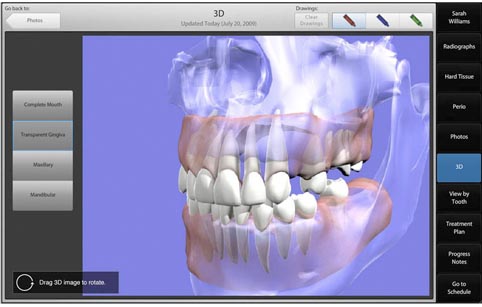

INFORMÁTICA DENTAL

Es un campo multidisciplinario que busca mejorar la atención de salud a través de la aplicación de la Tecnología de la salud y ciencias de la información a la atención de salud .

En el campo de la informatica dental tiene que ver con la intersección de informatica de la salud y odontología en su conjunto, esta es una área de interés dentro de la profesión, tanto en círculos académicos y entre los dentistas que ejercen más y más escuelas dentales y pro supuesto practicas dentales que están llevando a cabo los registros electrónicos de salud

Las exigencias de los programas federales y estatales para proveedores de atención medica. Como resultados de estos cambios, la odontología es la tecnología de la información atractiva para cumplir con su clínica, administrativa , la investigación y las necesidades educativas.